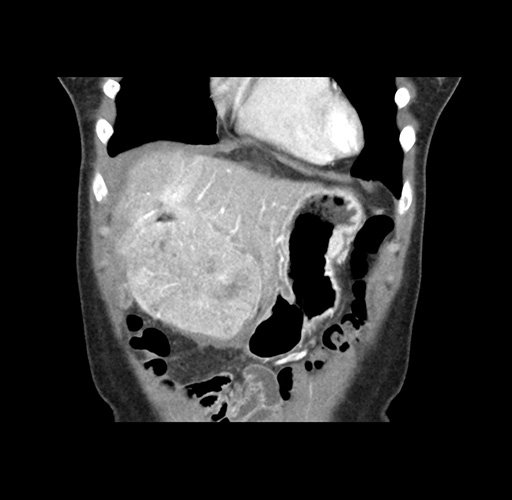

Imaging Analysis

Look through the patient's CT scan to identify any areas of concern for the necessary procedure.

Based on your CT findings, which issue(s) would give reason for "planned slowing down moment(s)" in this case?

Considering a standard left lateral sectionectomy procedure, what step(s) of the operation would you do differently in this case ?